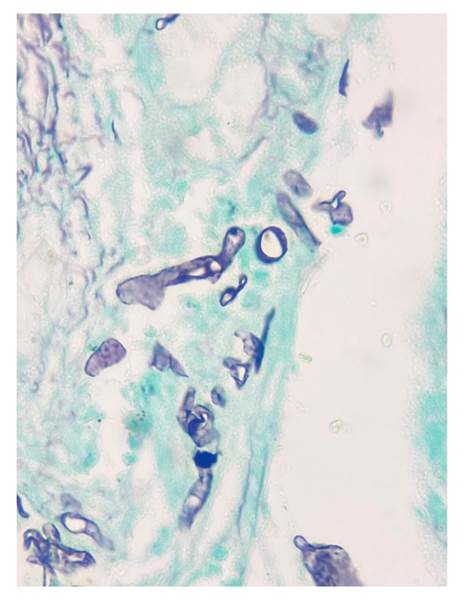

En todos los casos, se identificaron hifas anchas que variaban entre 5 y 20 pm, de contornos irregulares y pleomorfas. Su patrón de ramificación era al azar y, aunque predominaban en ángulo recto, algunas de ellas estaban colapsadas, organizadas en cordones o con doblamiento (figuras 2-5) 1.

Figura 3 Se reconocen hifas hialinas, gruesas, irregulares, seccionadas de forma transversal y sagital. Gomori-Grocott, 40X.

Figura 5 Se identifican hifas hialinas, irregulares, de diferentes formas y paredes gruesas, distribuidas de manera difusa sobre un estroma denso. Gomori-Grocott, 40X.